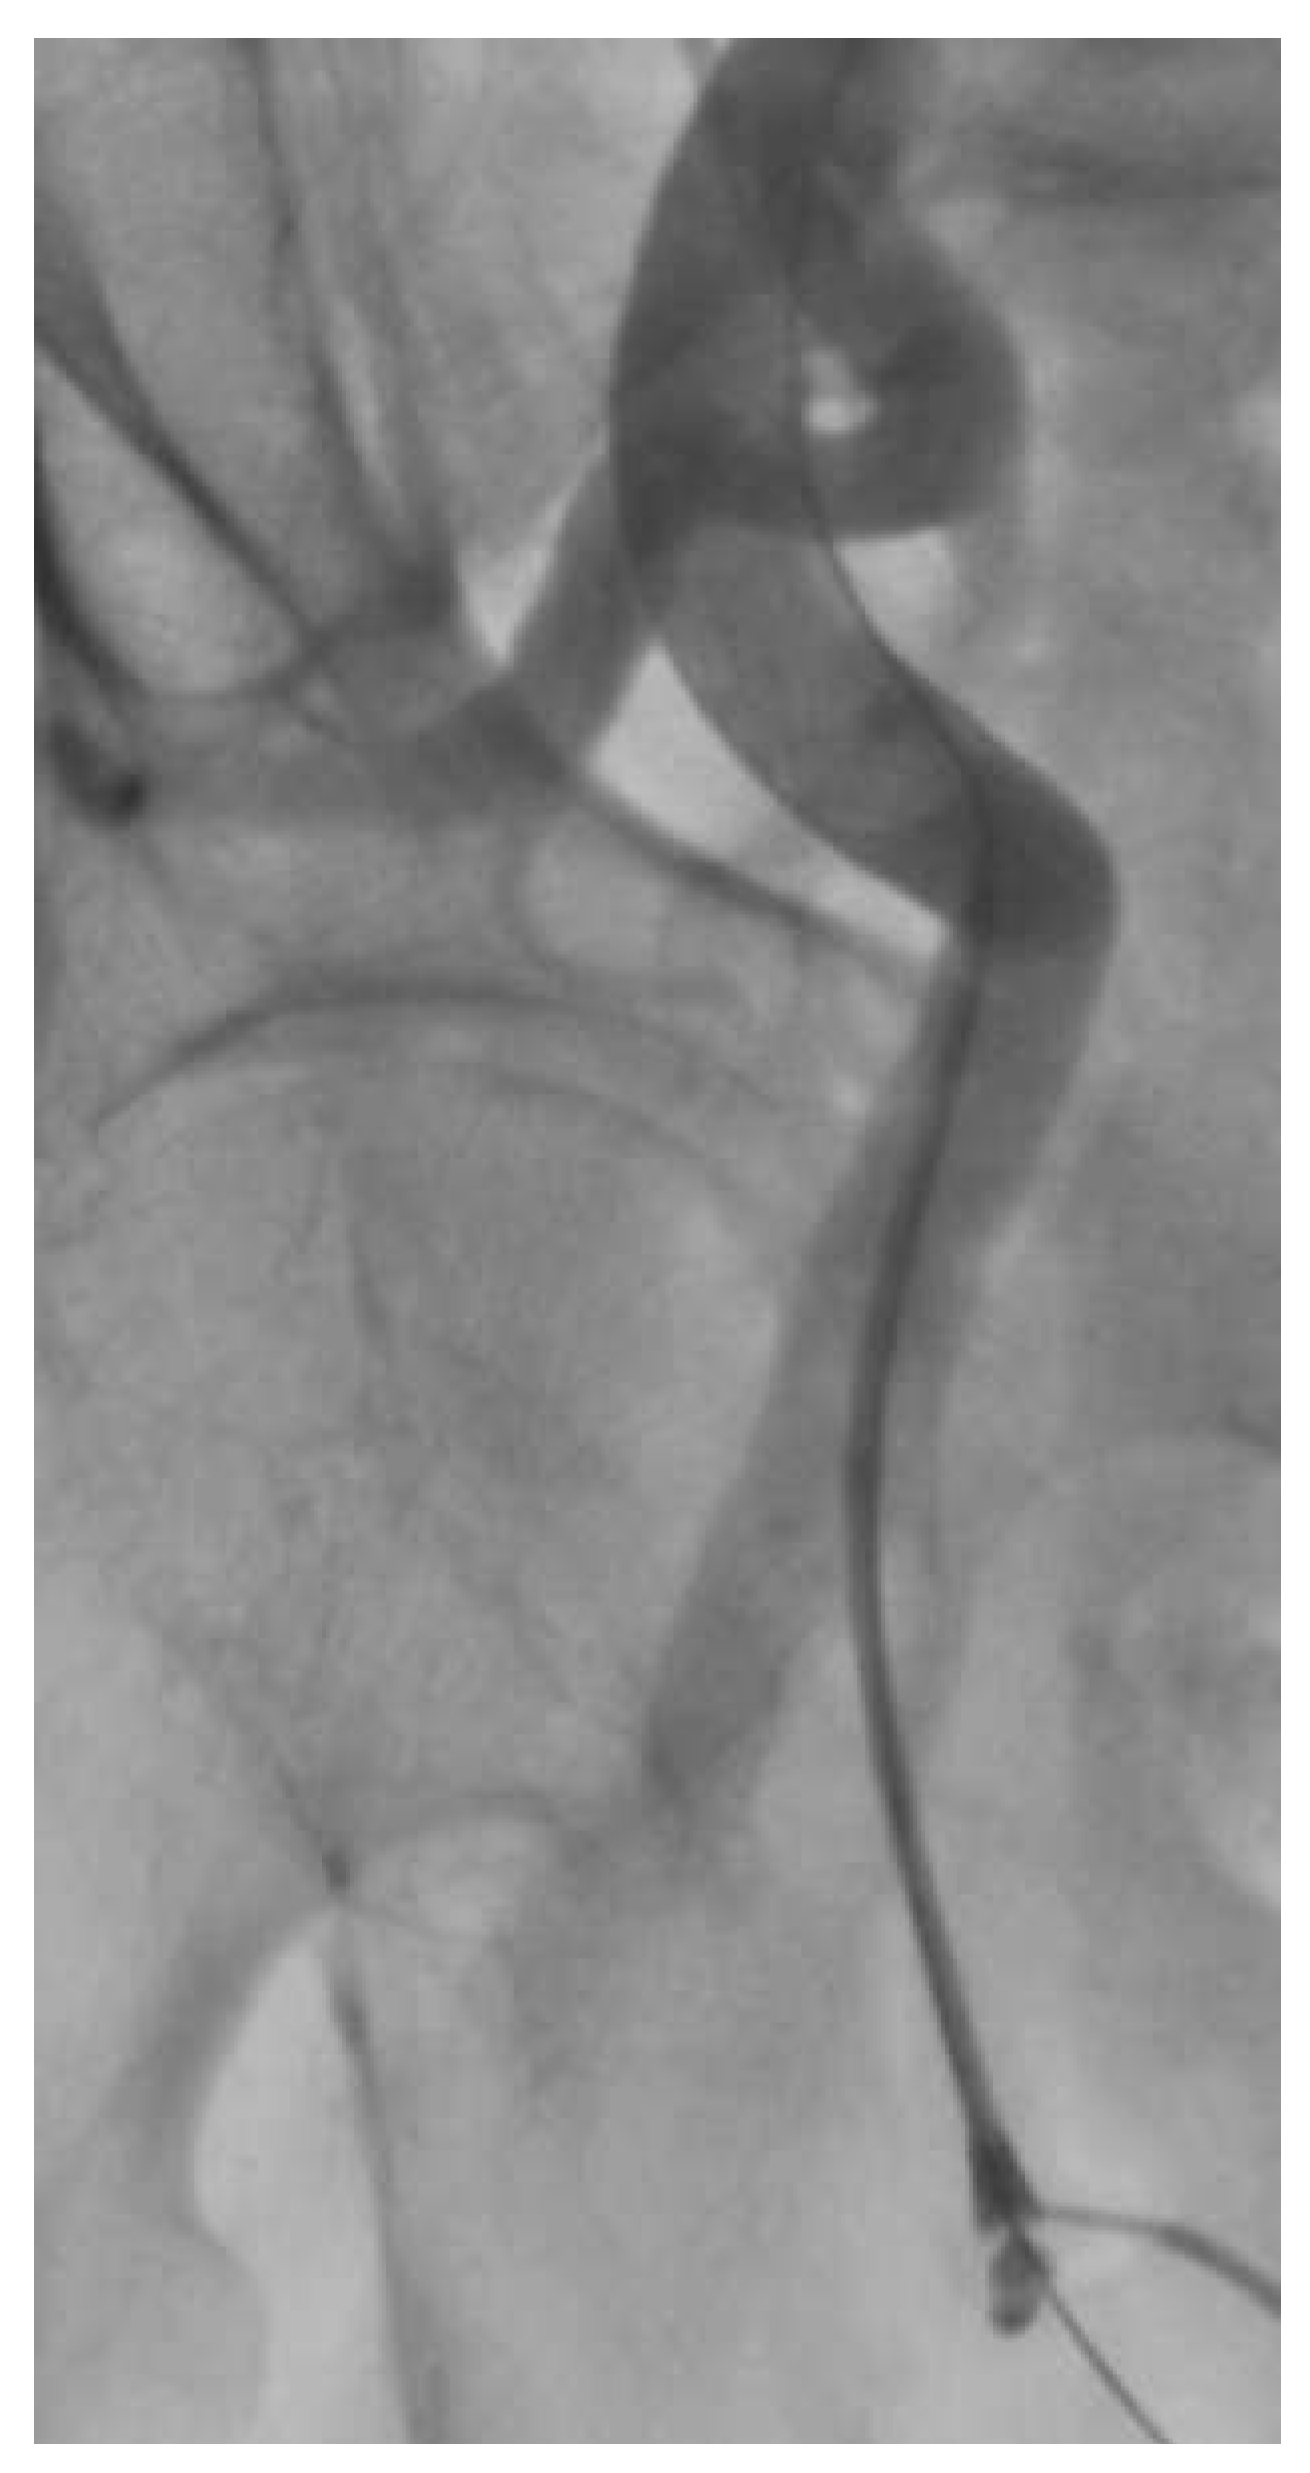

Under local anaesthesia and conscious sedation, we punctured the common femoral artery and performed the pre-closure technique using the Prostar® XL10 (Abbott Vascular, Reedwood City, CA). Over a Super Stiff ST-1 wire (Boston Scientific, Maple Grove, MN, USA) we inserted a folded 19-French SoloPath® sheath without any difficulties. As recommended by the instructions for use, once the sheath was full inserted we inflated the sheath balloon at 20 atmospheres for one minute. As we commonly did with other large-bore sheaths, the stiff wire was retrieved simultaneously with the dilator. At this time we noticed a kink in the sheath at the level of the iliac tortuosity (Figure 3), this kink was overcome with some difficulty by advancing a 0.035” wire. Subsequently, the kinked portion of the sheath was dilated with a peripheral balloon catheter (Admiral Xtreme 7 × 40 mm; Medtronic, MN, USA) (Figure 4). However, since we were not satisfied with that aspect of the sheath and we feared difficulties in advancement or retrieval of equipment during the procedure, we preferred to exchange the SoloPath® sheath for an 18-F Cook sheath (Cook Medical, Bloomington, IN, USA), which completely straightened the vessel (Figure 5). The procedure was then completed by pre-dilatation and successful implantation of a 29 Medtronic CoreValve®. The final ilio-femoral angiography from the contralateral femoral access showed no vascular complication or bleeding.

Figure 5. 18-F Cook sheath (Cook Medical) which straightened the ilio-femoral access.